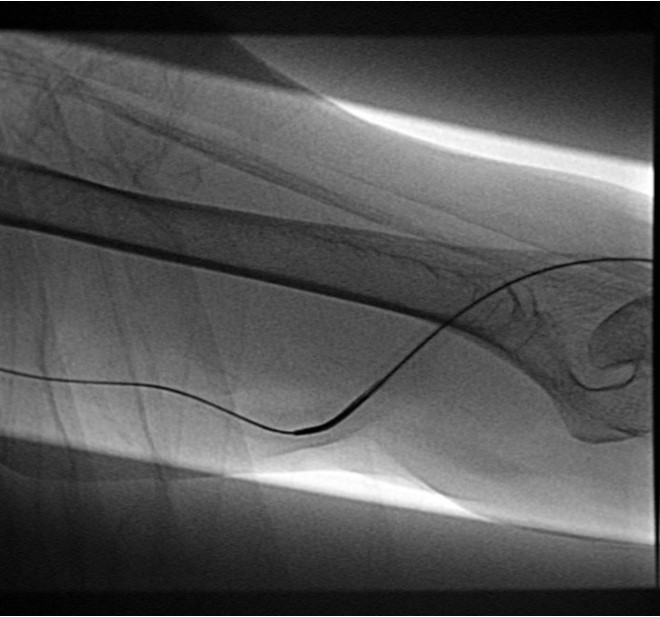

환자의 AV fistula는 초음파상 total thrombotic occlusion 된 상태였으며 시술 전 urokinase 100000 unit를 사용하여 thrombolysis and aspirated thrombectomy를 시행하였다. 그 후 시행한 shuntogram(Fig. 1) 상 left basilic vein 의 total ocdusion을 보이며 초음파상 remant vein의 크기는 1mm 이하로 확인되었다. 투시하에서 확인되는 outflow vein은 없었기에 초음파 유도하에 5 Fr Kumpe catheter(Soft-Vu, AngioDynamics, USA, NY) 에 0.035’ straight-tip guide wire(Terumo, Tokyo, Japan)를 사용하여 막힌 left basilic vein으로 15cm 이상 진행하였으며(Fig. 3), 4mm balloon (synergy, Boston, Ireland)를 사용하여 blind angioplasty를 하며 true lumen으로의 진행을 시도하였으나 실패하였다(Fig. 4). 더 이상의 antegrade로의 접근은 어려울 것으로 판단하여 regrograde approach를 위하여 left internal jugular vein 을 초음파 유도하에 9Fr sheath( Accu-Sheath, Sungwonmedical, Korea, Cheongju)을 사용하여 access 하였다. (Fig. 5A) 그리고 5Fr Cobra & sherpherd hook catheter (A&A M.D., Korea, Sungnam) 를 이용하여 left axillary vein으로의 접근을 시도하였다(Fig. 5B).

Fig. 3.

A-B. Guide wire negotiation into occluded left basilic vein with 4mm balloon

Fig. 4.

A-B. Failure of guide wire negotiation. Balloon tip was located in subcutaneous tissue.